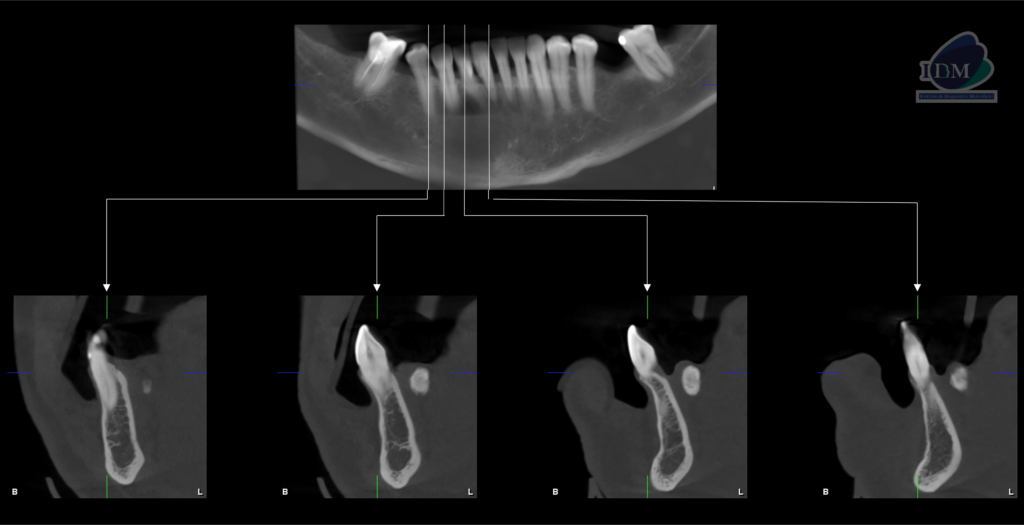

En la radiografía panorámica (Figura 1), se aprecia imagen radiopaca proyectada en tercio apical de pieza 43 y 44, de limites definidos.

Radiografia Panorámica

A la evaluación de la tomografía volumétrica (CBCT) en los cortes axiales (Figura 2) y transaxiales (Figura 3), se aprecia imagen hiperdensa de densidad cálcica localizada en lingual del cuerpo mandibular derecho a nivel de tercio apical de piezas 43 y 44, de limites definidos, forma irregular.